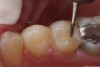

A patient presented for treatment with clinical and radiographic evidence of caries on the distal surface of the mandibular second premolar (Figure 1). The adjacent mandibular first molar had a defective amalgam restoration that was scheduled to be replaced with a core and prepared for a full crown at a future appointment. After administration of local anesthesia, a dental dam was placed. A sycamore wedge was firmly placed into the distal gingival interproximal embrasure before starting the preparation to achieve rapid separation of the tooth from its adjacent tooth to compensate for thickness of the thin, metal matrix (Figure 2). The tooth was prepared with a 245 bur with a high-speed handpiece and water spray. When restoring the proximal contact with composite resin, this author prefers to use a thin, dead-soft, stainless-steel matrix band that allows for shaping and achieving a positive, anatomic proximal contact. For this case the decision was made to use a silicone-covered split-tine ring with a sectional, thin, dead-soft, stainless-steel matrix. The silicone-coated ring is stable on the tooth and continues to apply pressure during restoration placement to ensure an anatomic proximal contact, while its shape allows for placement without interference from the gingival wedge. Also, the matrix has a tab extension that makes it easy to hold and place using a special forceps (Figure 3). Once the band was placed, an anatomic, flexible, polymeric wedge was placed using the same forceps.

Figure 2  Pre-wedging tooth for rapid separation

Figure 2